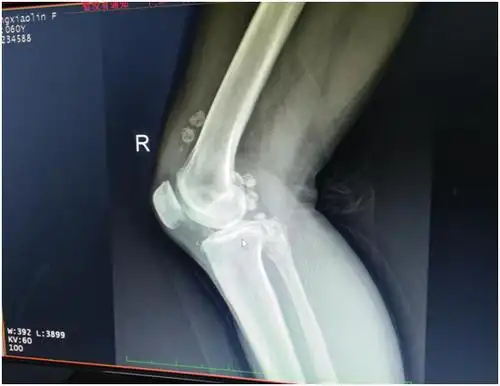

罕见!小小膝盖竟长了近30颗"关节鼠"